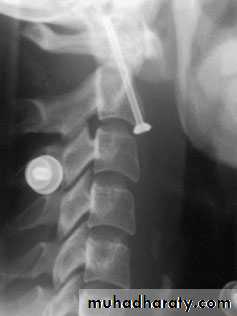

Fracture of C2 ‘Hangman’s fracture’ – fracture of

the pars interarticularis of C2.C2 Odontoid process fracture

C2 pars interarticularis fractures

‘hangman’s fracture’ there are• bilateral fractures of the pars interarticularis of C2 and

• the C2/3 disc is torn;

2. the mechanism is extension with distraction.

This is one cause of death in motor vehicle accidents when the forehead strikes the dashboard.

Neurological damage, is unusual

because the fracture of the posterior arch tends to

decompress the spinal cord.

Nevertheless the fracture

is potentially unstable.